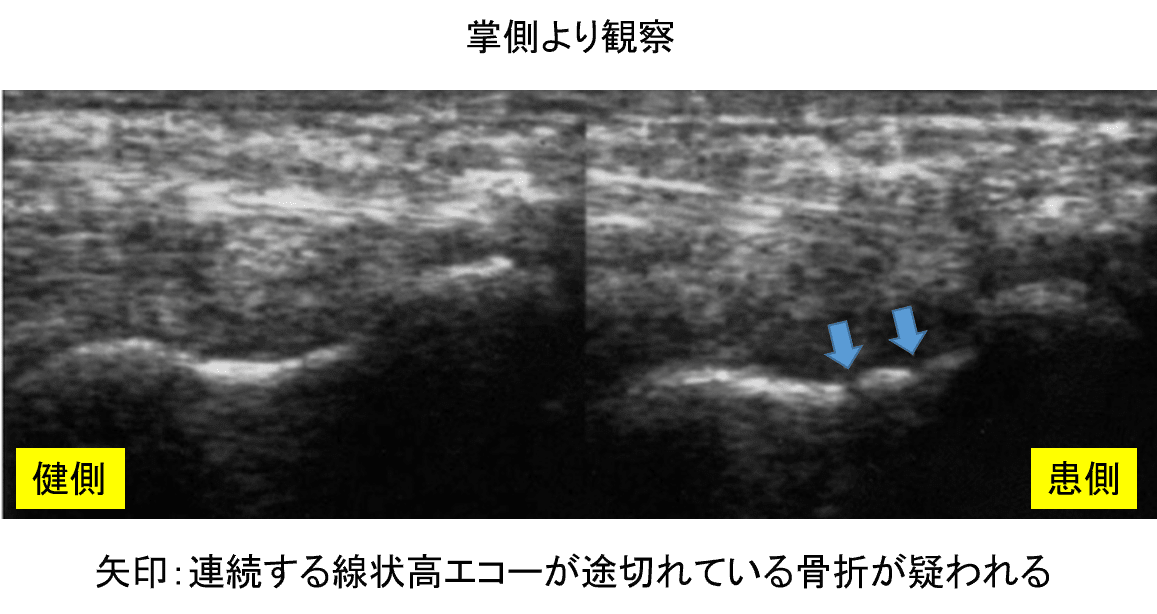

実症例のエコー画像

基本的には掌側からの観察となります

エコーを見ていきましょう

健患側と比較すること

👇線状高エコーが離断されているのがわかる